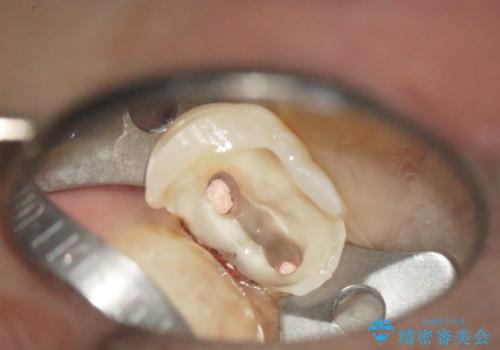

- 虫歯が深かったため、根管治療を行い、土台を立て直しかぶせ物を製作します。

虫歯で奥歯が真っ黒になり崩壊していましたが、悪い部分を完全に取り除き、丁寧に修復することでまた長く機能させることができます。